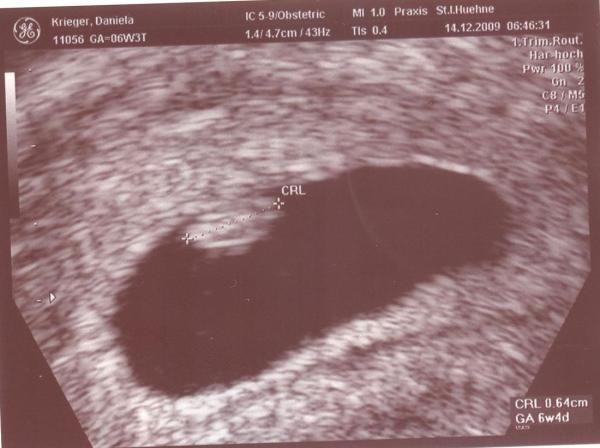

Hallo ihr lieben, ich komme gerad vom Arzt. Und alles ist super!! Krümmelchen ist 0,62 cm groß und das Herzchen blubbert kräftig! Der nächste Termin ist dann leider erst in 4 Wochen am 12.01...so eine warterei... Freuen uns auf jeden Fall riesig, auch wenn mir nach wie vor Hundeelend ist =)

Bild zu Erste Vu gehabt - Forum für August - Mamis